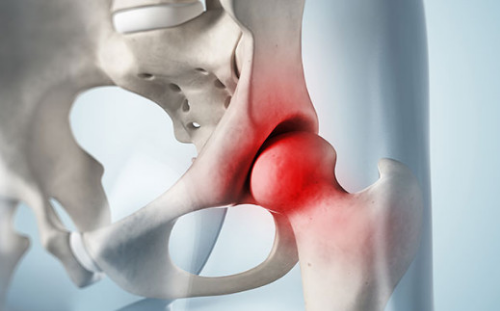

무혈관성 괴사는 혈액 순환에 문제가 생겨서 뼈가 손상되는 질병으로, 대퇴골두 무혈관성 괴사는 허벅지 뼈인 대퇴골의 머리 부분에 혈액 공급이 원활하지 못해 일어납니다. 이 질병은 주로 30~50대에서 발생하며, 남성에 더 많이 나타납니다. 60% 이상의 환자가 양쪽 고관절의 대퇴골두 무혈관성 괴사를 겪습니다. 이 질병을 일으키는 위험 인자로는 음주, 부신피질 호르몬 투여, 고관절 부위 외상, 잠수병, 통풍, 혈청지질 이상, 만성 신질환, 만성 췌장염 등이 있습니다. 특히 음주와 부신피질 호르몬제가 전체 원인의 90% 정도를 차지합니다.

대퇴경부 골절은 대퇴 골두로 향하는 혈관 손상으로 인해 대퇴 골두에 무혈성 괴사와 골 불유합을 유발할 수 있습니다. 따라서, 응급 내과적인 절차로 대퇴 골두를 치료하는 수술이 필요합니다.